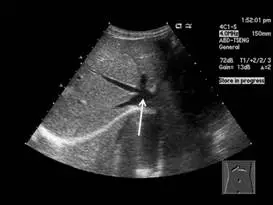

附圖為肝臟超音波影像,箭號所指為何?

- 這是一張典型的肝臟灰階超音波影像,掃描切面靠近肝臟上方(近橫膈膜處)。

- 影像中可見數條「無回音(anechoic,呈現黑色)」的管狀構造,且這些血管的管壁沒有明顯的高回音(hyperechoic,呈現亮白)特徵。

- 這幾條血管(右、中、左肝靜脈)在肝臟實質內匯集成一個較大的血管。這個經典的影像呈現被稱為「兔寶寶徵象(Playboy bunny sign)」,其中「兔子的耳朵」代表肝靜脈(Hepatic veins),而「兔子的頭」則代表這些靜脈匯流進去的下腔靜脈(Inferior vena cava, IVC)。

- 題目中的白色箭頭正是指著這些肝靜脈共同匯流的較大管狀構造,即為下腔靜脈。